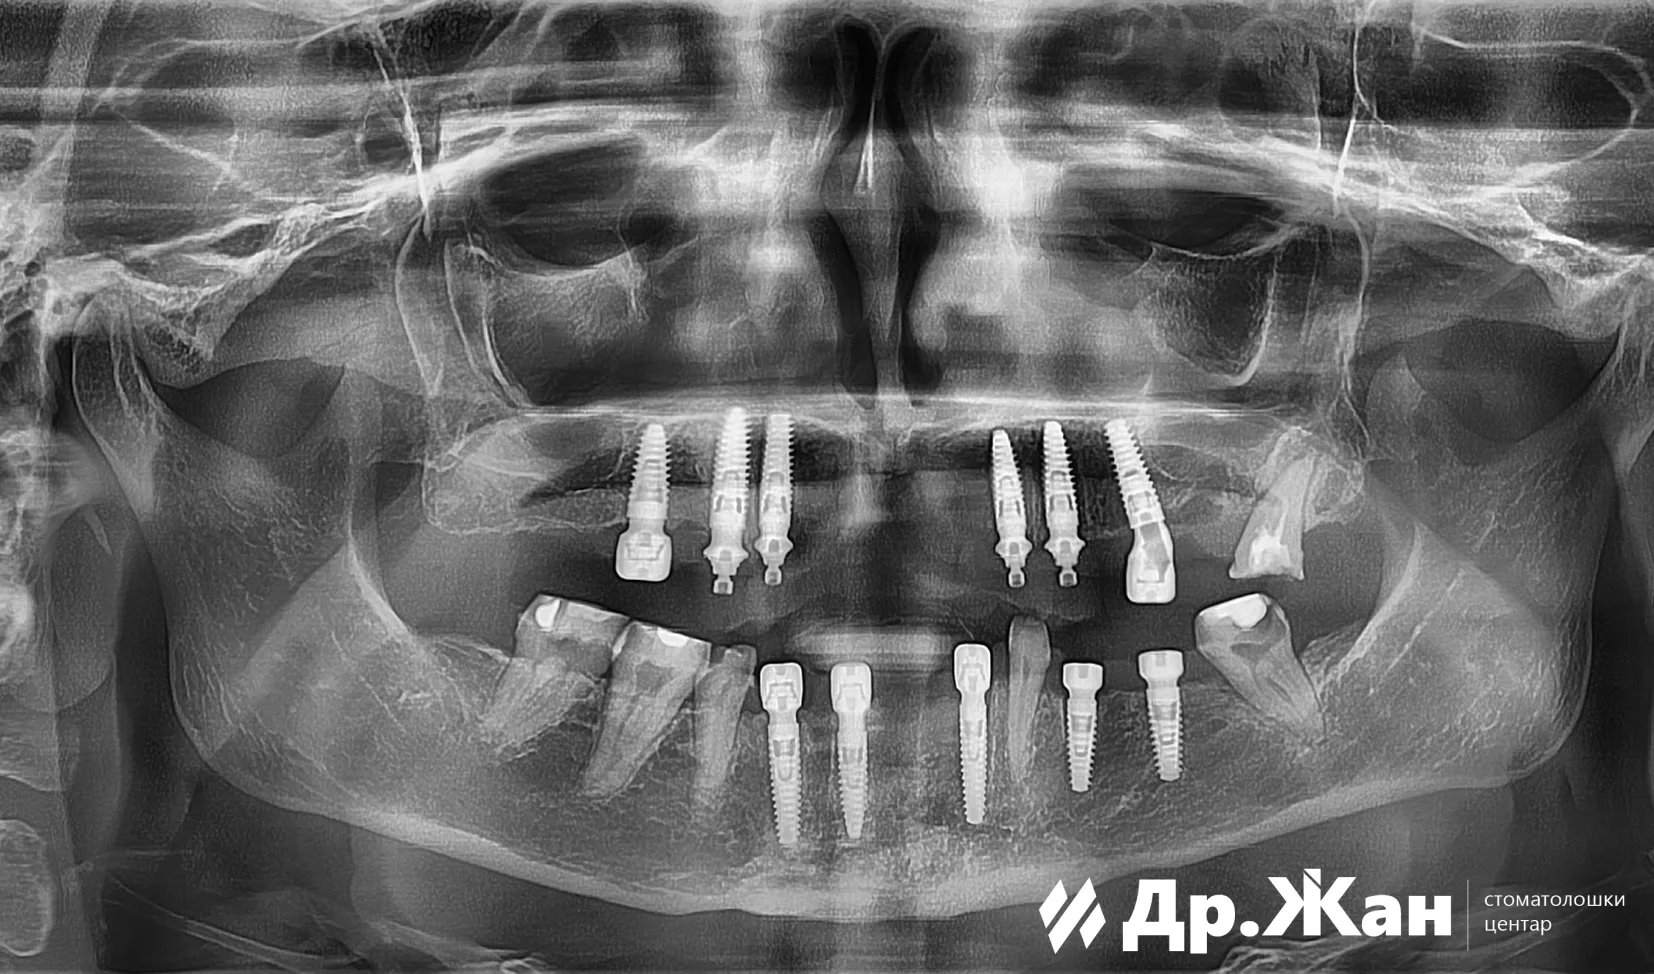

По внимателно испитување и анализа, планот беше да се извлечат сите заби во горната вилица, а некои да се задржат во долната вилица за полесен премин за пациентката. Веднаш по вадењето, беа поставени 6 импланти во горната вилица и 5 забни импланти во долната вилица. Имплантската терапија беше извршена со дигитален работен тек и со употреба на хируршки водичи. ѝ беа обезбедени фиксни привремени заби за периодот на заздравување.

По 6 месеци заздравување и остеоинтеграција на забните импланти, пациентката се врати за нејзина финална реставрација. Случајот беше тежок III степен со унапредување на долната вилица. Но, со користење на дигитален работен тек и детално планирање, беше направена тотална реконструкција на устата со хибридна циркониум-титаниумска конструкција и циркониумски коронки и мостови. На оваа прекрасна пациентка ѝ беше обезбедена убава, нова, функционална и естетска насмевка.

ПОТОА